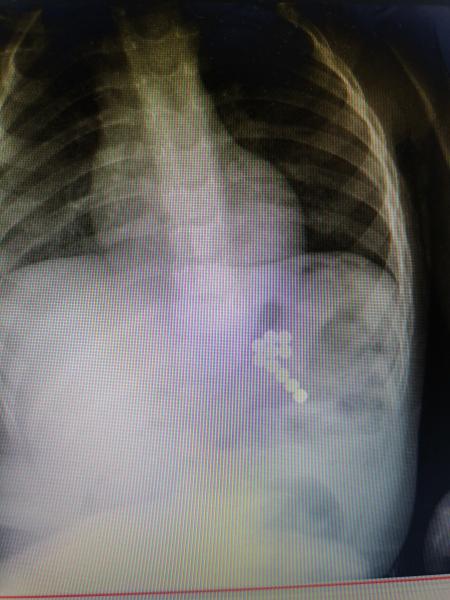

手术前腹部X线片检查

近日,家住泸溪县合水镇的2岁幼儿因莫名腹痛、不吃东西、呕吐,当地乡镇卫生院诊断为“胃肠炎”,治疗6天后病情愈发严重,遂至泸溪县人民医院。经腹部X线检查,确诊为“消化道异物”“消化道穿孔”“急性弥漫性腹膜炎”,随后紧急转往我院治疗。

追问病史,发病6天前,患儿爷爷曾带孩子到亲戚家玩耍,亲戚家10岁小孩有磁力珠这种玩具,考虑到消化道异物已经存留多日,且导致胃肠穿孔,需急诊手术。经普五科急会诊及术前准备,于入院当日晚在急诊全麻下行剖腹探查术,术中见“胃两处穿孔”、“近段小肠三处穿孔”、“部分小肠因肠梗阻缺血坏死”。遂行胃肠穿孔修补、坏死部分小肠切除及断端一期吻合,同时从胃肠道及腹腔内取出磁力珠十枚。术后经过抗炎、营养支持,伤口换药等处理,患儿痊愈出院。